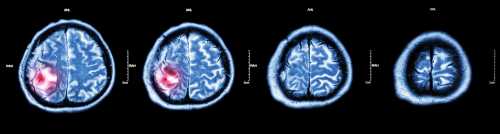

Опухоль головного мозга: основные симптомы

Диагноз